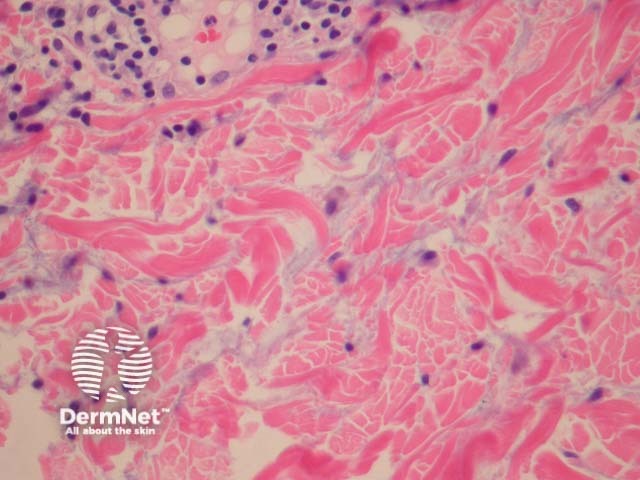

In REM, sections show a superficial and deep perivascular and periadnexal mononuclear infiltrate (figure 1). The epidermis is uninvolved. The presence of copious mucin between collagen fibres of the dermis is characteristic of the disorder (figures 2, 3).

Figure 2

The mucin may be difficult to appreciate on routine H-E sections. Special stains for mucin (such as colloidal iron or hyaluronic acid) can be helpful to confirm the presence of dermal mucin.